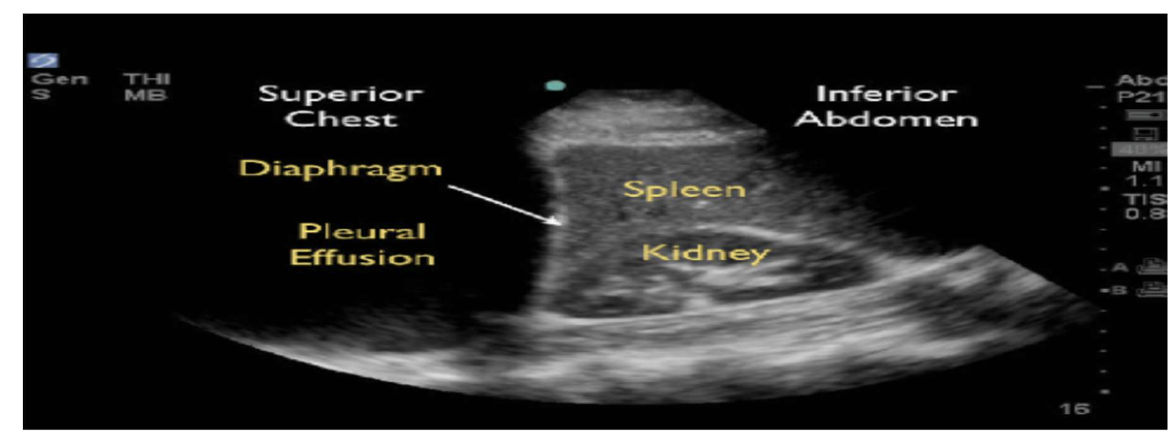

Chest ultrasound

Biopsy of chest wall, mediastinal and peripheral lung masses

• Diagnostic and therapeutic drainage of pleural fluid collections and

• Assessment of soft tissue masses of the chest

aid in the detection

of lymphomas, retrosternal thyroids, dermoid cysts or aortic aneurysms with

this ultrasound chest approach

CHEST US INTERVENTION

• Diagnostic and therapeutic drainage of pleural fluid collections

• Moveable strands, fibrinous strings and septations are typical of

inflammatory effusions.

• Ultrasound can detect nodular metastases not seen in radiographs